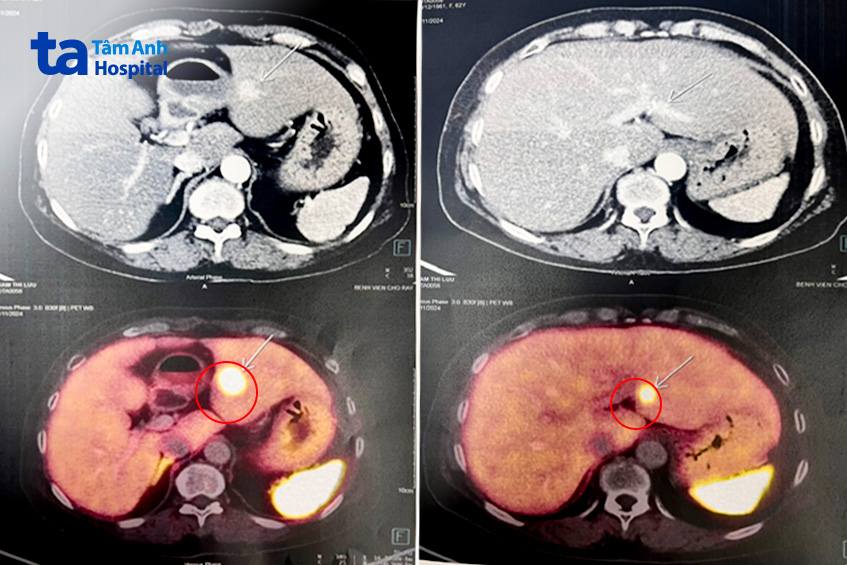

Bất ngờ, kết quả chụp CT Scan toàn thân cho thấy 6 khối u rải rác khắp cơ thể, gồm 2 khối u tuyến cận giáp hai bên, kích thước 1,2cm và 1,7cm; 1 khối u ở vú phải; một ở gan và 2 u ở tụy. Kết quả chụp mạch máu số hóa xóa nền (DSA) và siêu âm nội soi, bấm sinh thiết, xác định u ở gan và tụy là u thần kinh nội tiết.

Ổn định sau phẫu thuật tuyến giáp, người bệnh được tiếp tục điều trị các khối u gan và tụy còn lại. “Mặc dù là u không tiết (u không có hoạt động nội tiết tố), không có triệu chứng nhưng nếu cứ để vậy thì các khối u sẽ tiến triển có thể chuyển thành ung thư”, bác sĩ Trâm nói. Khối u ở thân tụy có kích thước dưới 2cm, chưa đủ điều kiện để phẫu thuật, sau khi hội chẩn các bác sĩ quyết định sử dụng công nghệ nội soi đốt sóng cao tần (RFA) để đốt khối u này. Tuy nhiên khi kiểm tra sâu, phát hiện ống tụy đi ngang qua khối u nên không thực hiện được, nếu không sẽ gây ra viêm tụy cấp nên chỉ thực hiện đốt u gan. Khối u tụy tiếp tục được theo dõi và điều trị nội khoa.

“Điều đáng lo ngại nhất của người bệnh này là đa u tuyến nội tiết tiến triển đã di căn gan, tiên lượng còn rất dè dặt và cần theo dõi sát”, bác sĩ Trâm cho biết thêm. Hiện tại bà Long đã được cắt bỏ khối u gan tại chỗ, hạn chế di căn, đồng thời điều trị để kiểm soát các triệu chứng liên quan đến tiết hormone, kiểm soát sự phát triển của bệnh, theo dõi u vú qua siêu âm vú mỗi 6 tháng và nhũ ảnh mỗi năm.